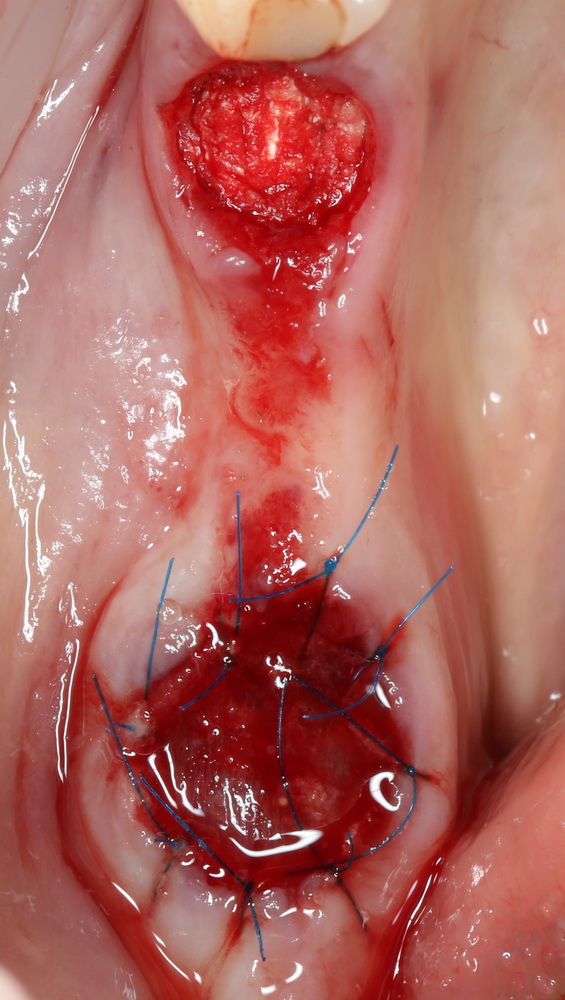

Очень аккуратно удалили зуб. Убрали из лунки все грануляции. В область верхушки корня зуба — Neocones, остальная часть альвеолы — Bioss Collagen. Сама лунка запечатывается Mucograft Seal:

Который подшивается к ее краям:

Пациенту даются обычные рекомендации после удаления зуба. Контрольный осмотр — через день:

И вот тут я подумал, что пришла беда. Решил, что Mucograft Seal развалился (пациент курит), что с дня на день нужно ждать альвеолит.

Но оказалось иначе. Никаких беспокойств, никаких проблем, никакого дискомфорта. Сняли швы через неделю, с пациентом расстались на полтора месяца.